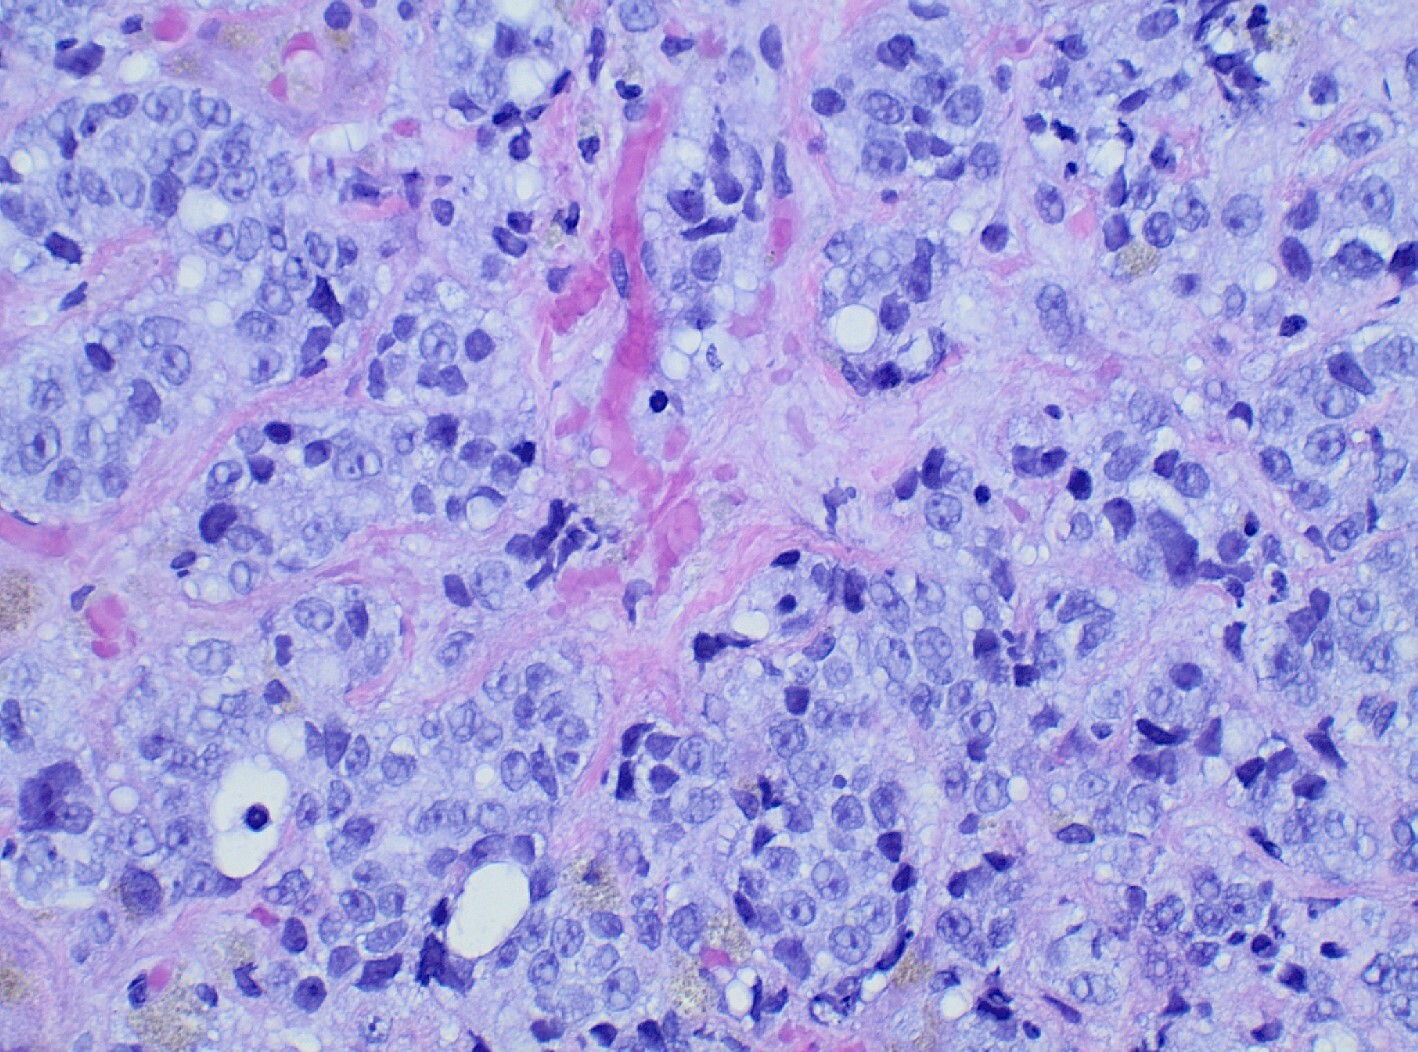

Diagnostic paracentesis was performed and revealed an ascitic protein of 0.9 g/dL, and serum-ascites albumin gradient was calculated to be 2.8. Given his prior history of docetaxel use, the decision was made to proceed with a trans-jugular non-targeted liver biopsy to rule out medication induced hepatic veno-occlusive disease. Hepatic venous pressure gradient was found to be elevated at 32 mmHg. The liver biopsy revealed infiltrative adenocarcinoma from known primary prostate cancer with immunohistochemical staining significant for positive NKX 3-1 and negative CK7 and CK20 (Figures 1-5). The patient was diagnosed with ALF secondary to infiltrative prostate cancer and did not meet transplant criteria due to malignancy. Considering the information provided via the liver biopsy, it was determined the lutetium (177Lu) vipivotide tetraxetan therapy would be ineffective. After extensive conversation, the patient and his family opted for home hospice to spend valuable time with loved ones. The patient was discharged after a total hospital stay of 6 days. He expired less than 2 weeks after discharge.